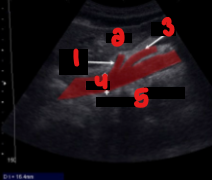

Label the crossed-out structures on this image.

Celiac artery

Liver

SMA

Aorta

Vertebra